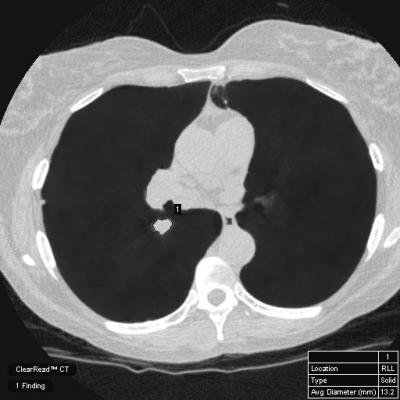

Radiologists spend a significant amount of time on mundane reporting and measurement processes. ClearRead tools help overcome this based on increased automation and can help radiologists improve the efficiency of disease detection, diagnosis, reporting, and treatment.

- Demonstrate the FDA-cleared and CE-marked ClearRead bone and vessel suppression AI tools that takes advantage of the latest innovations in AI.